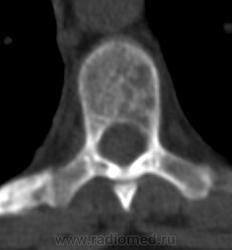

Костное окно:

Я всегда с интересом отношусь к "высоким технологиям", но, как свидетельствуют данные, картинка тел пораженных позвонков при миеломе очень напоминает "картинку мозга"...

По имеющимся файлам-дайком я не нашла признаков опухоли. Имеется множественное остеолитическое поражение позвоночника, ребер, грудины, частично - таза. Лимфоузлы не увеличены. Тоже поставила бы на первое место миеломную болезнь. Диагностирование её не всегда простое дело. Поражена грудина и, наверное, нужно посоветоваться с онкологом (гематологом) стоит ли сделать стернальную пункцию.Советую написать в личку tatyana.